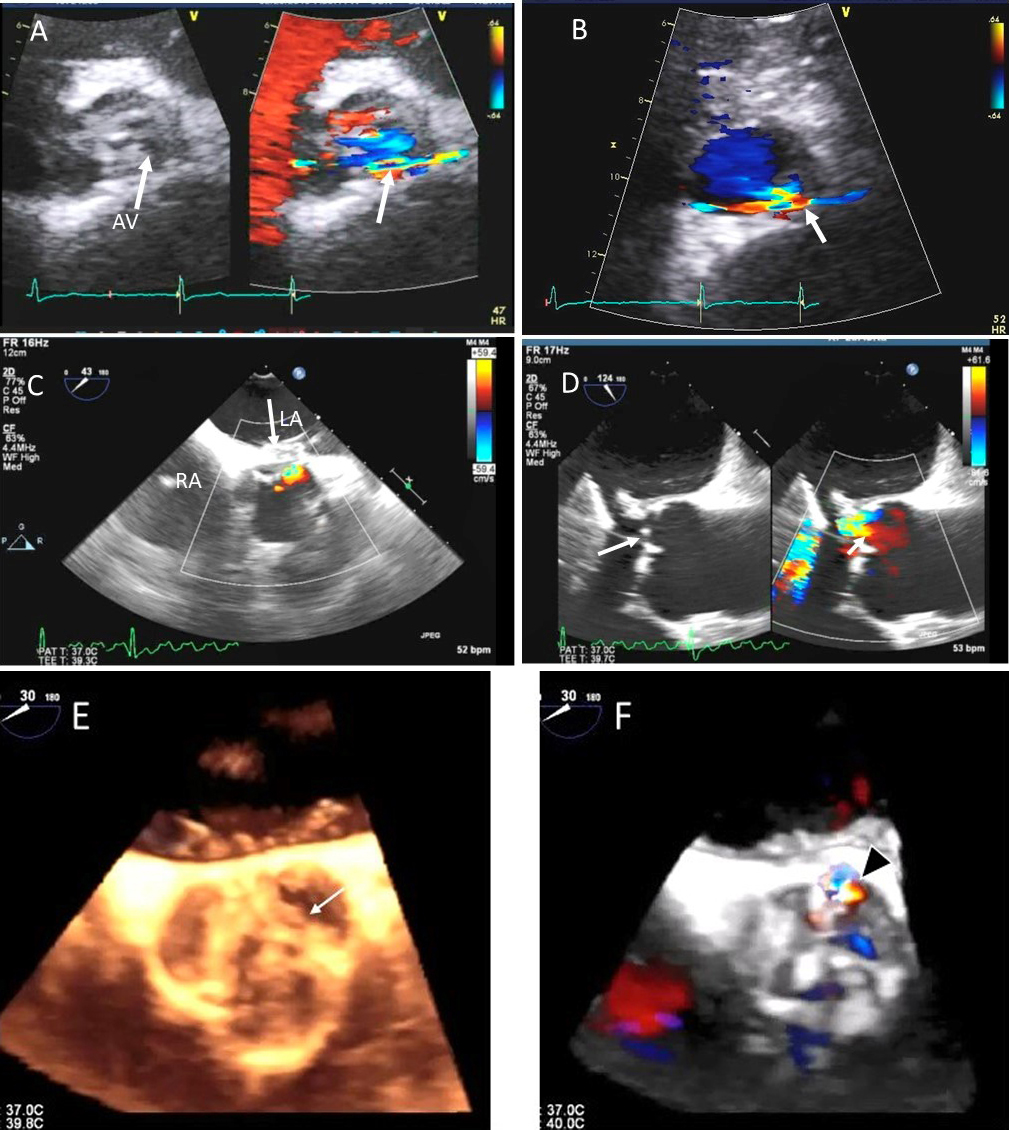

Besides prolapsing or flail scallops, MR jet may also originate between individual scallops. This occurs more commonly between the posterior leaflet through cleft like indentations that sometimes extend to the mitral annulus. This origin of MR can be very difficult to diagnose on 2D TTE or TEE (Fig. 2A–C). 3D color Doppler further assists in confirming jet origin at the site of suspected leaflet pathology/ies including presence of mitral valve cleft like indentation/s. Presence of calcification on the annulus and leaflets and in the subvalvular apparatus further assists surgeon in planning repair [21]. Visualization of the valve from the LV perspective adds further information on leaflet morphology, coaptation and regurgitant site/s particularly if jet originates from mitral valve clefts. Optimal visualization of the MR jets using real-time 3D TEE leads direct guidance for catheter movement and positioning of the implanted device(s) capturing the opposing sides of anterior and posterior mitral leaflet scallops during catheter based MV interventional procedures [22].

Fig. 2.Mitral leaflet Cleft. (A) TTE short axis at the mitral valve level showing posterior mitral cleft. (B, C) Isolated cleft within the P2 segment of the posterior leaflet (associated with mitral regurgitation) on 3D TEE and TTE short axis views. AML, anterior mitral leaflet; PML, posterior mitral leaflet.

Fig. 8.Aortic regurgitation and left coronary cusp perforation. (A) TTE color Doppler parasternal short axis view demonstrating left coronary cusp perforation (white arrows), resulting in aortic regurgitation. (B) TTE color Doppler short axis view showing origin of aortic regurgitation through the left coronary cusp perforation (white arrow). (C) TEE color Doppler short axis view showing a better delineation of the origin of aortic regurgitation jet through the left coronary cusp perforation (white arrow). (D) TEE long axis view demonstrating the perforated coronary cusp on 2D (white arrow) with aortic regurgitation jet originating through the perforation (white arrow) and not through the aortic leaflet coaptation. (E) 3-dimensional (3D) TEE short axis view of the aortic valve showed a clear definition of the left coronary cusp perforation (white arrow). (F) 3-D TEE color Doppler short axis view showing aortic regurgitation jet originating through the left coronary cusp (black arrowhead). Direct planimetry of color Doppler aortic regurgitant orifice can be performed online or via offline post processing of 3D data sets without geometrical assumptions of PISA method or continuity equation.

Common causes of leaflet malfunction causing AR include degenerative leaflet calcifications, and infective endocarditis (Fig. 10), bicuspid aortic valve perforation and rheumatic fever. The causes of AR include Marfan’s syndrome, annulo-aortic ectasia (idiopathic root dilatation) (Fig. 9), aortic dissection, connective tissue disease, and syphilis. The Carpentier classification is also widely used to describe the mechanism of AR [63].

Fig. 10.Endocarditis induced aortic cusp tear and aortic regurgitation (AR) demonstrated by TEE: (A) TEE transgastric (TG) view showing dense CW Doppler signal of AR with a steep slope, (B) Mid esophagel (ME) long axis view showing torn and flail aortic valve cusp, (C), same view showing severe AR on color Doppler, (D) ME short axis view showing a tricuspid aortic valve, (E) TEE TG view showing dilated LV and severe AR on color Doppler and (F) torn AV leaflet on 2D. (G) transthoracic parasternal long axis view showing a dilated LV and poorly defined AR on color Doppler, (H) transthoracic AV short axis view with an ill-defined view showing possible of the torn left coronary cusp (white arrow).

Using 2D biplane, 3D and 3D color Doppler, the exact perpendicular plane to the aortic regurgitation jet can be identified, from which planimetry of the AV coaptation gap as well of the color Doppler vena contracta can be performed [64]. This has been shown to have a good correlation with aortographic grading of AR. When the shape of the regurgitant orifice is nonsymmetric, by using 3D images, invalid geometric assumptions of the vena contracta can be avoided with direct measurement [65]. 3D echocardiographic color Doppler also allows visualization, and measurement of multiple jets and correlated morphologically with surgical findings [65].

Isolated aortic valve perforation can occur post endocarditis or post cardiac surgery [15, 16, 17]. Restriction of aortic valve leaflet motion may occur due to leaflet tethering [18, 19]. Combined use of 2D, color Doppler and 3D TEE may facilitate location and mechanism of AR and can allow valve repair instead of replacement.